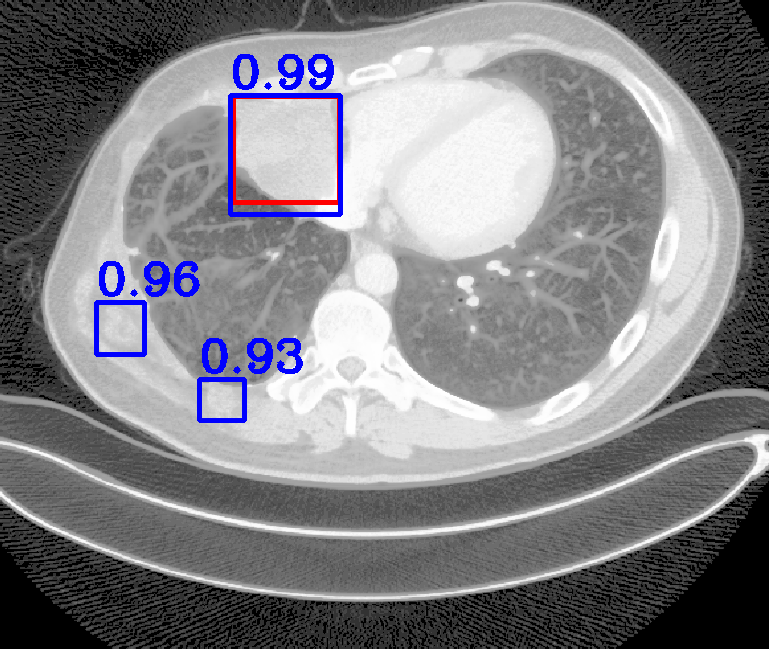

| (a) Ground Truth | (b) Faster R-CNN | (c) FPN | (d) Proposed |

In real-world scenarios, body lesions usually have arbitrary size. For instance, in the DeepLesion [14] dataset, the lesion size ranges from 0.21 mm to 342.5 mm. Since most of the established CNNs are not robust to handle such spatial scale variations, they have unpredictable behavior in the varying cases. As shown in Fig. 1, both Faster R-CNN and FPN fail to detect tiny lesions in the first row, while they produce small false positive lesions around the actual large lesion locations in the second and third rows.